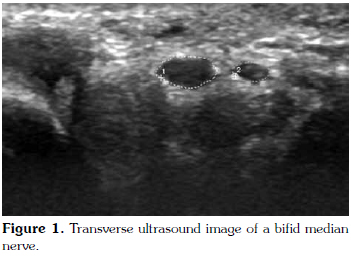

Ultrasonographic examination: After clinical and electrophysiological diagnosis of CTS, patients were referred to the radiology clinic and underwent ultrasound (US) examination. The ultrasonographic evaluation was performed by a radiologist who was blinded to the clinical and electrophysiological evaluation, using 12-17 MHz linear array transducers (Aplio XG, SSA 790A, Toshiba Medical Systems Corporation®, Nasushiobara, Japan, 2011). Participants were seated facing the examiner with arm along the shoulder and elbow flexed, the forearm lying on the knee. The full course of the median nerve in the tunnel in axial and sagittal planes was evaluated. If the median nerve was divided into two branches proximal to the carpal tunnel, it was considered as BMN (Figure 1).